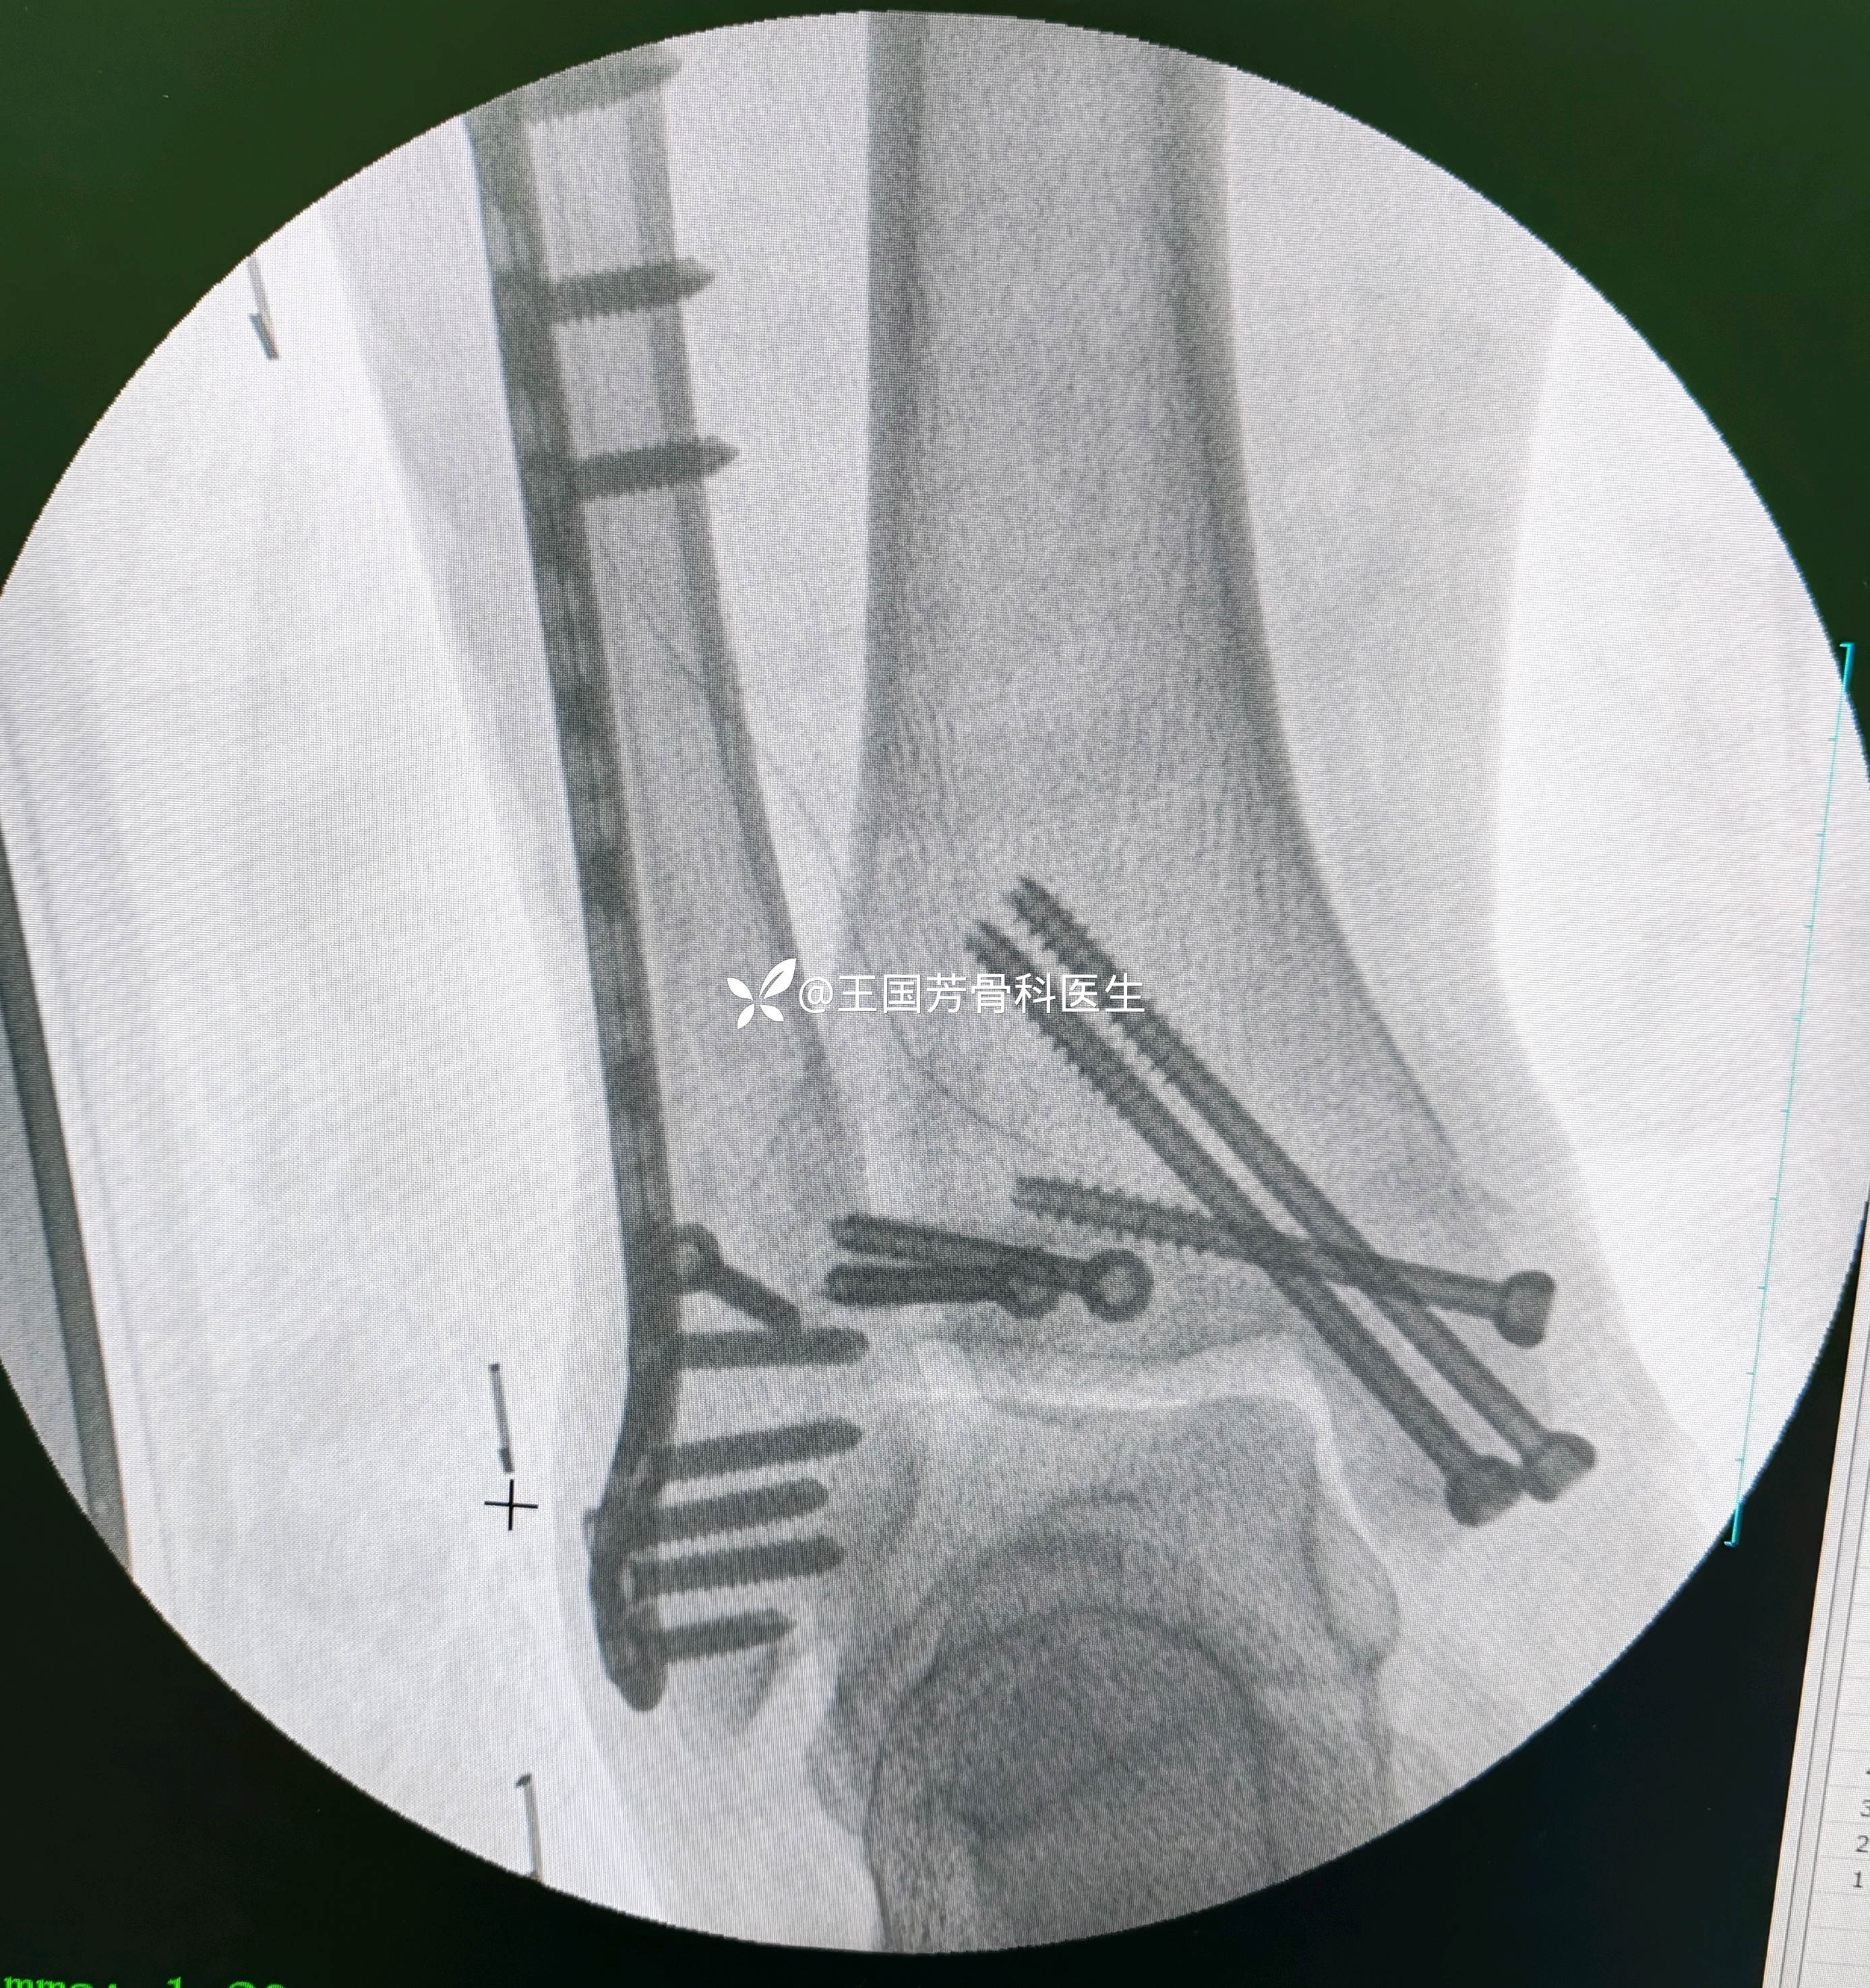

晚上10点开始手术,11点半结束,手术顺利

术中透视

术后换药,拔引流管,无皮肤坏死。